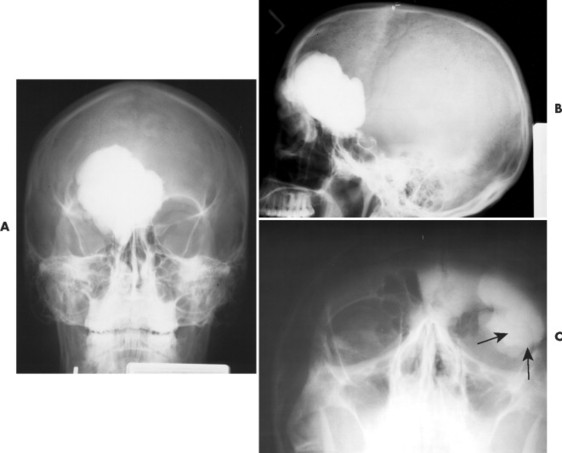

Остеома и мукоцеле левой лобной пазухи

Мукоцеле лобной пазухи

Остеома лобной пазухи